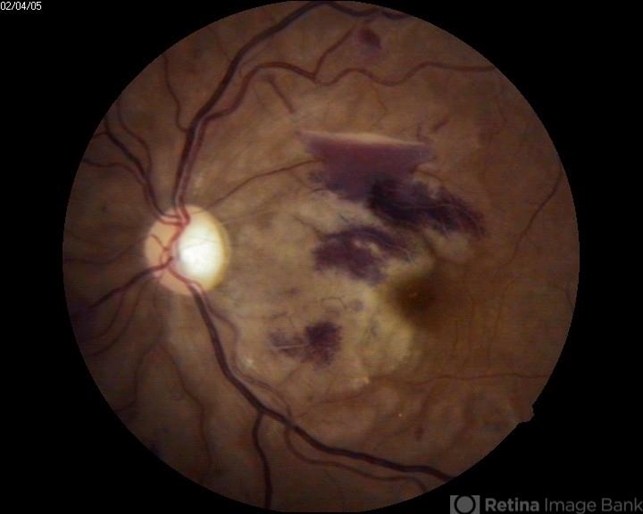

- fibrous macular scar

- A 24-year-old patient had blunt trauma having macular scar.